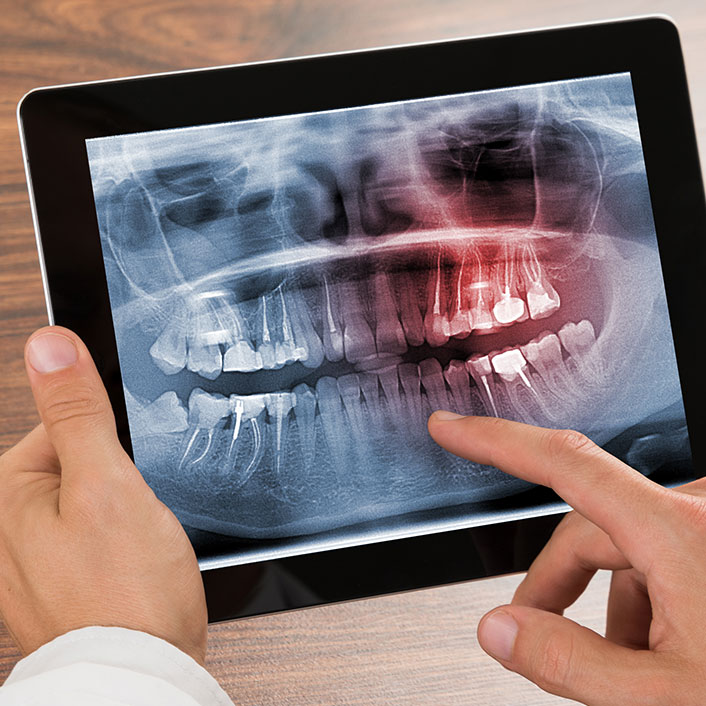

RADIOGRAFIAS DIGITAIS

Radiografia Panorâmica

Laudos e Análises Radiográficas